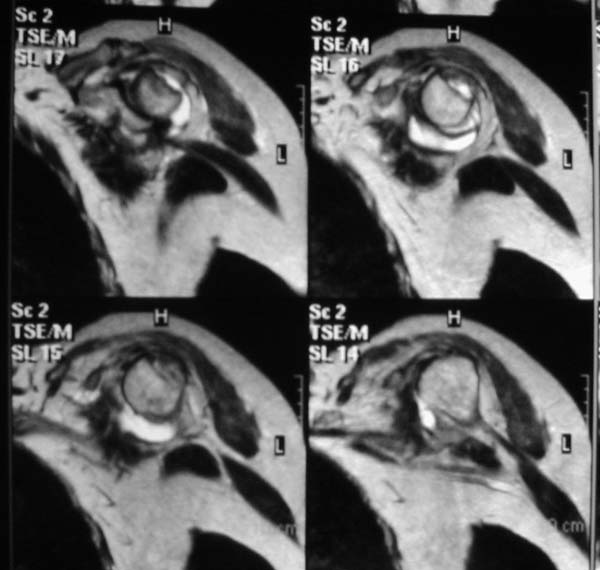

В приложенном файле - МРТ изображение. Более информативно, чем предыдущий вариант? менее? или также?